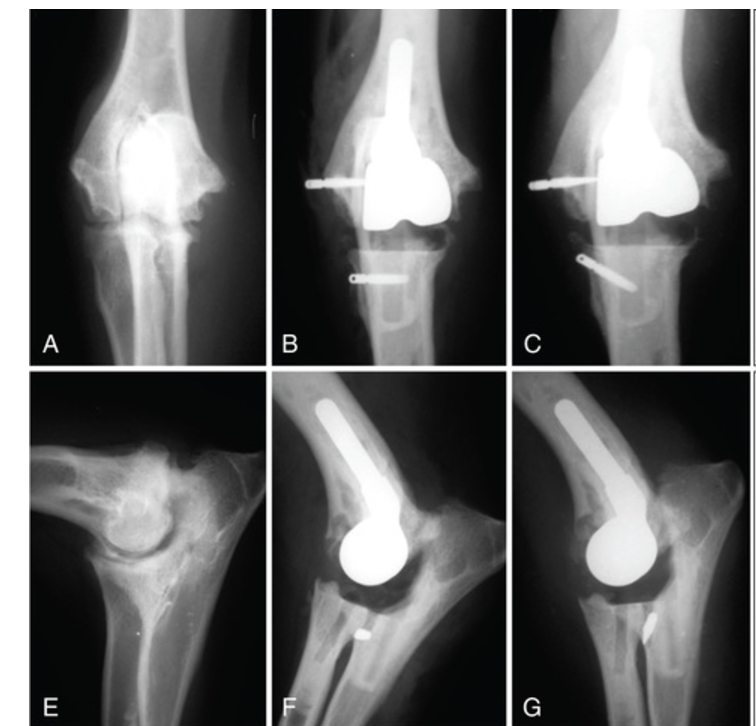

Q

Iowa state

11

Tate